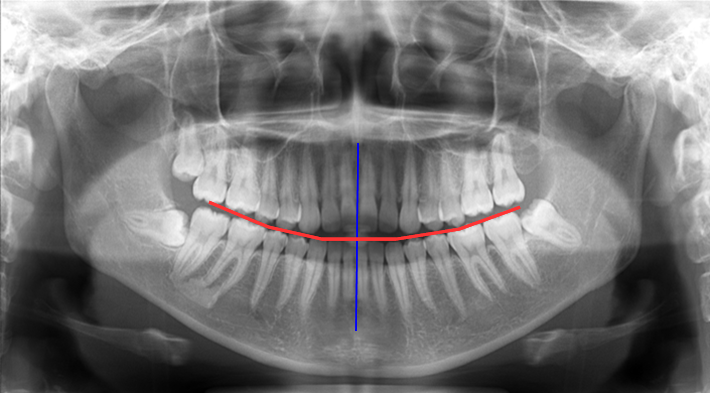

【正常な咬合関係】 |

正常な噛み合わせは、正中が合っており、左右ほぼ対称です。

前後の噛み合わせも平面的であるため、ズレることなくしっかり咬むことが出来るわけです。 |